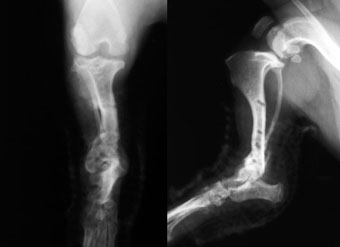

写真下段: プレート除去後

手術から17か月後にプレートを除去しました。

(膝関節に入れられていたプレートも除去しています) |